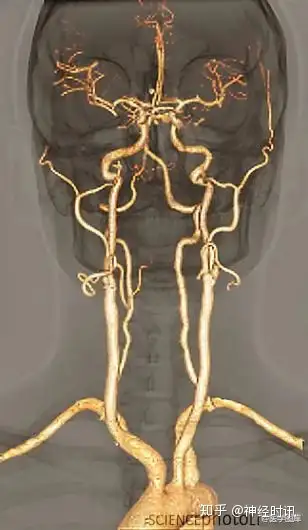

大脑供血动脉3D扫描CT成像